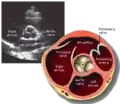

A transthoracic echocardiogram (TTE) is the most common type of echocardiogram, which is a still or moving image of the internal parts of the heart using ultrasound. In this case, the probe (or ultrasonic transducer) is placed on the chest or abdomen of the subject to get various views of the heart. It is used as a non-invasive assessment of the overall health of the heart, including a patient's heart valves and degree of heart muscle contraction (an indicator of the ejection fraction). The images are displayed on a monitor for real-time viewing and then recorded.

This view is obtained in the same window as the parasternal long, but with the probe rotated 90°. In this view, the aortic valve is seen in cross-section with the right ventricular inflow & outflow tracts visible with the tricuspid valve as well. Pulmonary valve is not visible in this view. Both the right and left atria are visible.

The standard PSAX view is at the level of the aortic valve, but moving the probe along the long-axis can review the LV outflow tract, LV at the base, and LV at the midsection.

Structures visible:

- Aortic valve in short-axis

- Aortic valve dysfunction, aortic sclerosis/stenosis

- Tricuspid valve in long-axis

- Pulmonary valve in long-axis

- Right ventricle, including inflow and outflow tracts

- Left ventricle in short-axis